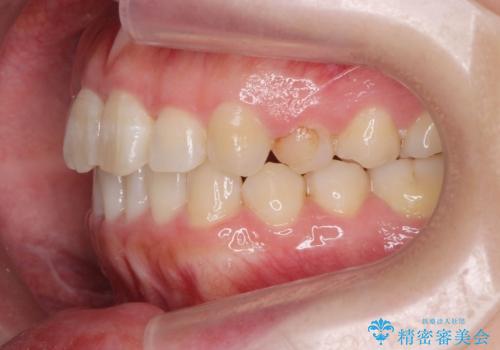

前歯のねじれをマウスピース矯正インビザラインで治療

- 長年気になっている、前歯のねじれの矯正治療を希望され来院されました。

十分にマウスピース矯正インビザラインで治療が可能と判断し、治療を進めることとしました。

長年気になっていた前歯のねじれが、ワイヤーをつけることなく矯正を行うことができ、大変喜んでいただくことができました。